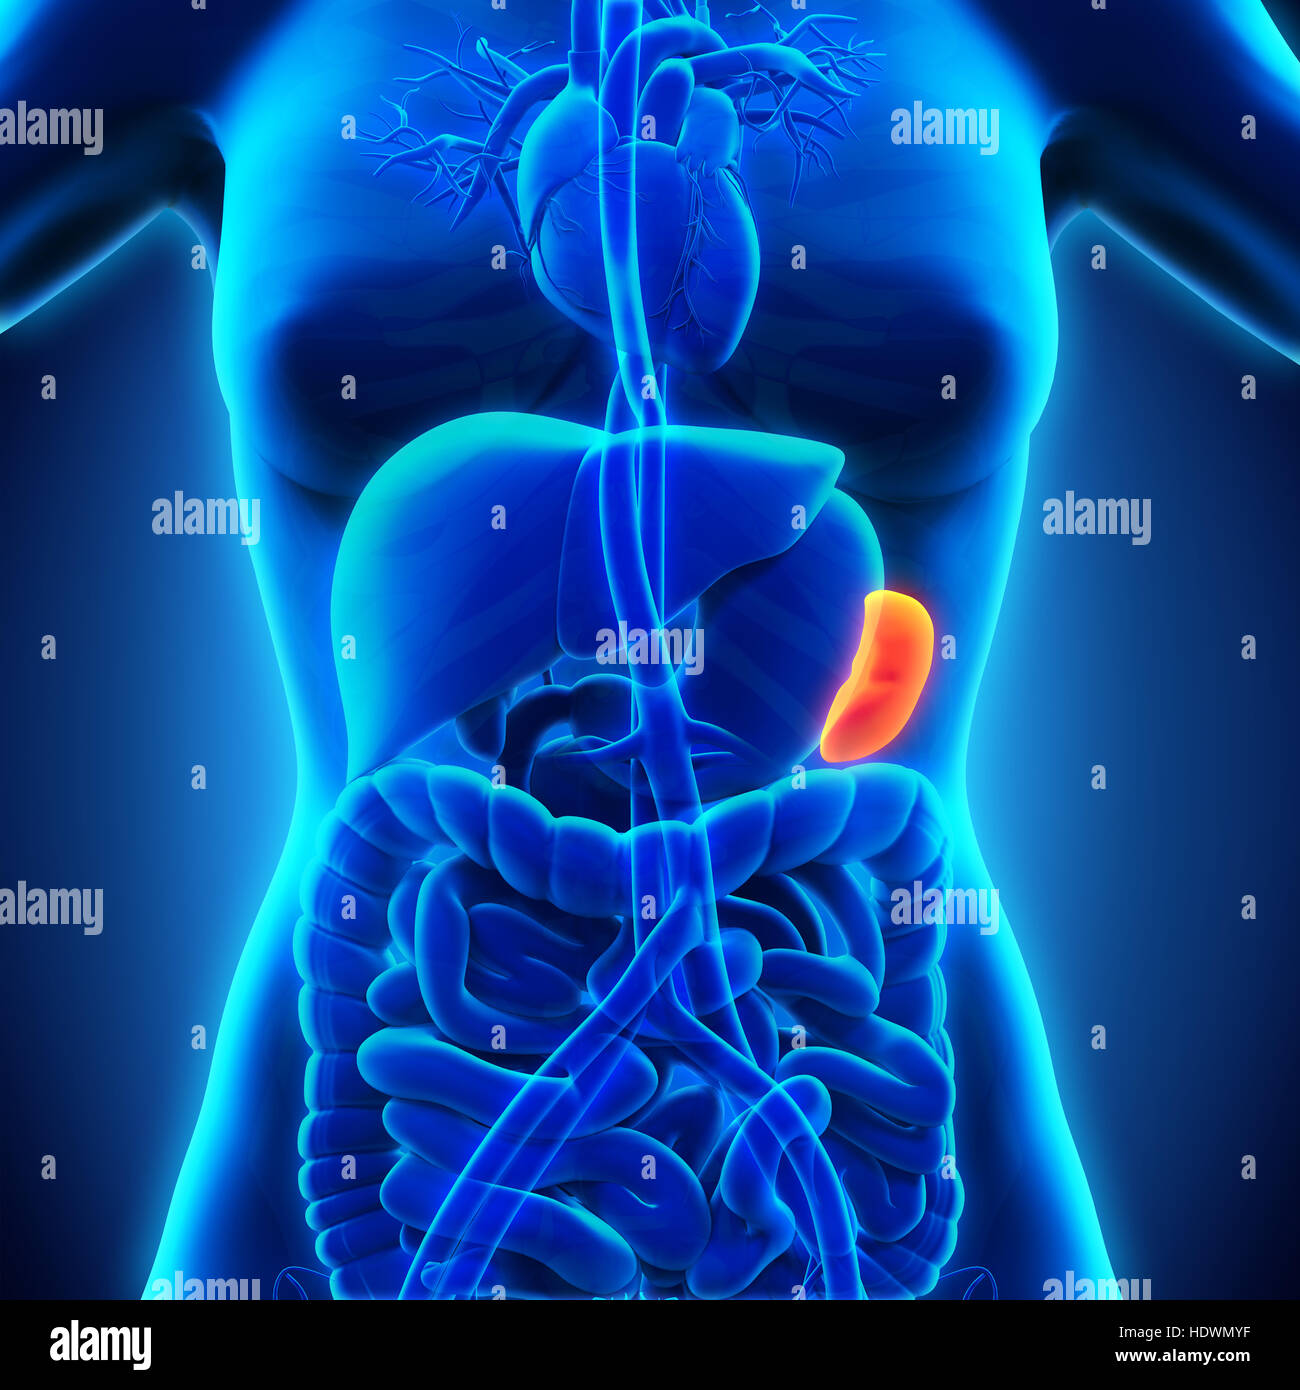

Illustration de l'anatomie de la rate femelle Banque D'Imageshttps://www.alamyimages.fr/image-license-details/?v=1https://www.alamyimages.fr/photo-image-illustration-de-l-anatomie-de-la-rate-femelle-74913780.html

Illustration de l'anatomie de la rate femelle Banque D'Imageshttps://www.alamyimages.fr/image-license-details/?v=1https://www.alamyimages.fr/photo-image-illustration-de-l-anatomie-de-la-rate-femelle-74913780.htmlRFE9TH84–Illustration de l'anatomie de la rate femelle

Les droits de l'anatomie de la rate Banque D'Imageshttps://www.alamyimages.fr/image-license-details/?v=1https://www.alamyimages.fr/photo-image-les-droits-de-l-anatomie-de-la-rate-129028355.html

Les droits de l'anatomie de la rate Banque D'Imageshttps://www.alamyimages.fr/image-license-details/?v=1https://www.alamyimages.fr/photo-image-les-droits-de-l-anatomie-de-la-rate-129028355.htmlRFHDWMYF–Les droits de l'anatomie de la rate